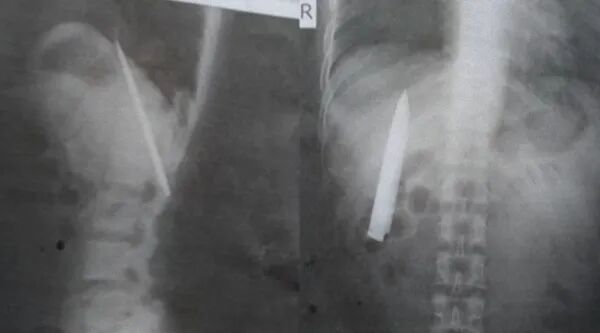

胸部里竟然有把刀,菲律宾男子气炸了

菲律宾25岁男子托莫(Kent Ryan Tomao)近日去一间采矿公司面试,他被要求去做常规入职体检。没想到,X光检查出他的胸部里竟有一把刀!刀长10厘米且非常靠近肺部,情况相当危急。托莫惊呆:“难怪我常在天气冷的时候胸口痛”。托莫表示,去年1月他曾被数名少年持刀攻击,而医护当时仅告知他伤口很浅,缝合后便让他回家了……

现在发现刀子竟被遗留体内,托莫相当愤怒。但托莫经济拮据,因此他没有计划对该医院采取法律行动,只强调“该院当时未对他进行完整身体检查,因此该院对此负有责任,我希望他们能帮我免费把刀取出来,让我可以赶快工作。”